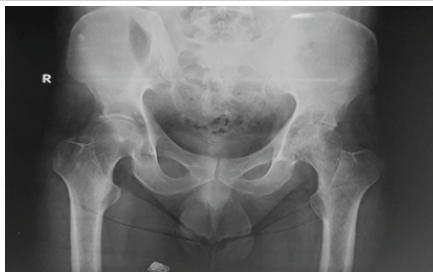

A 52-year-old male with CKD on maintenance hemodialysis for 5 years presented with gradually worsening left hip pain and reduced mobility over 18 months. Clinical examination revealed painful restriction of motion. Radiograph (Fig. 1) and magnetic resonance imaging showed advanced destructive arthritis of the hip. A two-stage surgical procedure was planned. In stage one (Fig.2), thorough debridement was performed, and an antibiotic-impregnated cement spacer was placed (Fig.3). Intra-operative tissue cultures grew Candida guilliermondii. The patient was treated with intravenous Caspofungin for six weeks, after which inflammatory markers normalised.

Figure 1: Pre-operative Radiograph demonstrating advanced destructive arthritis of left hip